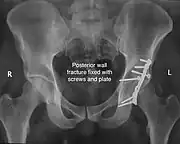

Posterior wall fracture fixed with screws and plate